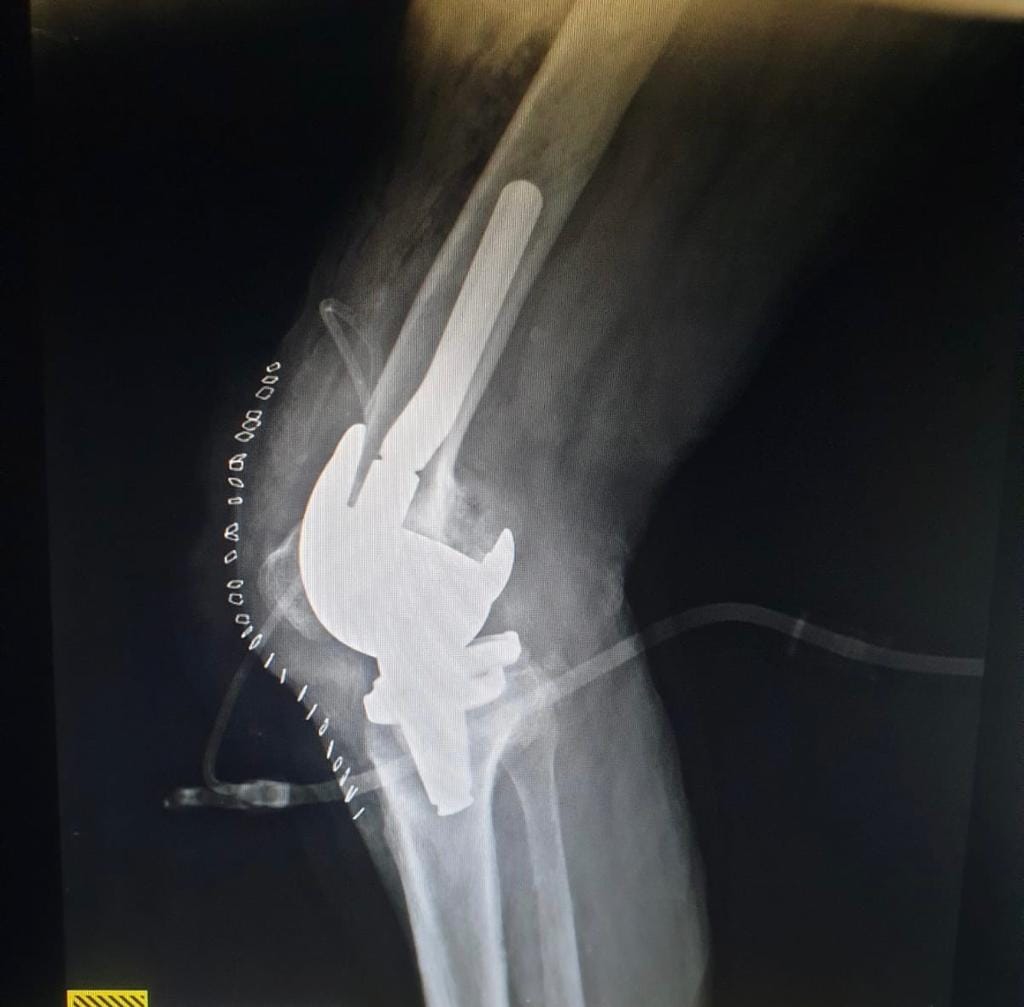

اجريت له العملية الجراحية

والمريض الان بحالة جيدة و الحمد لله.

وتألف الفريق الجراحي كلا من اخصائي جراحة العظام والكسور د. هادي عبدالله و د. فريد السوداني و د. يوسف علاء و اخصائي التخدير د قاسم عبدالله .